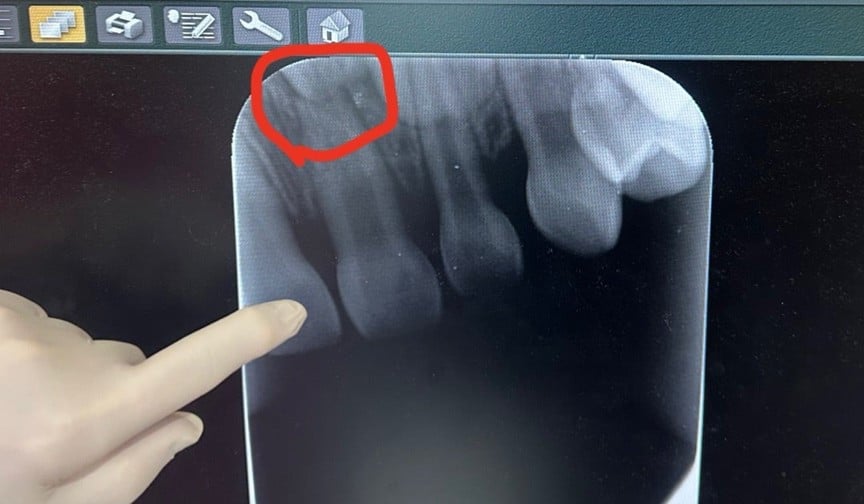

『あいのり』桃、3歳次男の前歯が灰色に…歯科検査で「神経が死んでいる可能性」